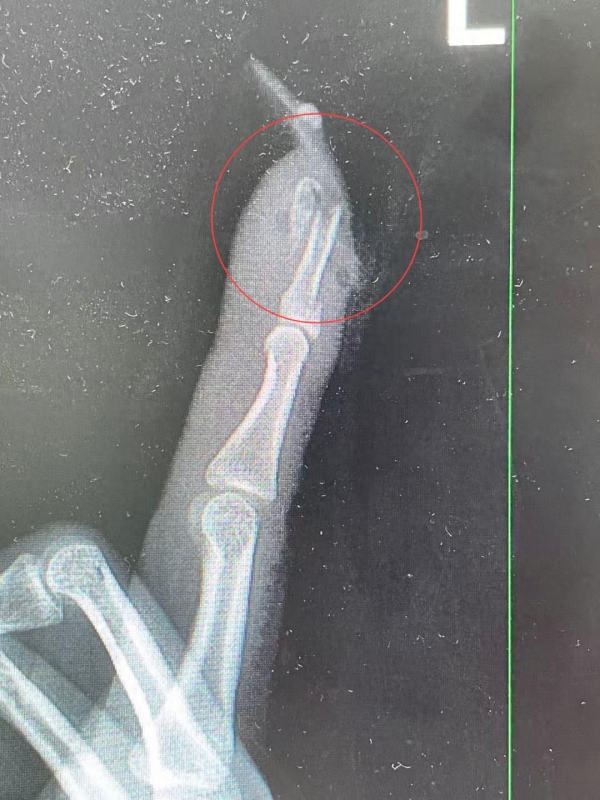

王小姐术前的X光影像

"如果没有这么细长复杂的美甲,伤害也许不会这么严重。"曹立表示,"延长甲片增加了手指的受力面积和杠杆作用,在摔倒时极易形成'撬动'效应,导致指甲撕脱、甲床损伤,甚至引发骨折。"